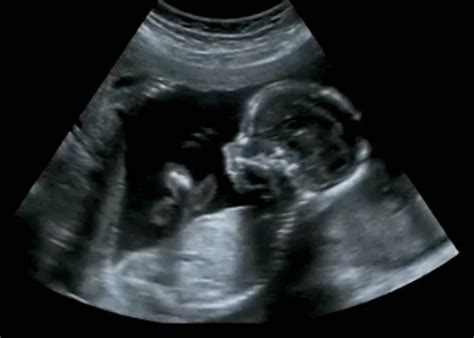

A magzat elhelyezkedését ultrahanggal lehet a legpontosabban meghatározni. A szülés módjának megválasztása általában a terhesség 36-37. hetében történik, figyelembe véve a magzat pozícióját, méretét és az anyai medence adottságait.